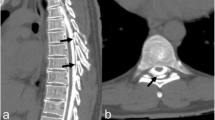

On the fourth postoperative day, however, the patient developed chest pain, dyspnoea and headache. The chest drain output increased to a total of 700 ml of clear fluid over the next 24 h and chest radiograph revealed bilateral pleural effusion (Fig. 3). The fluid drained from the chest drain tested positive for β2-transferrin (a sensitive marker for CSF). These findings led to the diagnosis of a subarachnoidal pleural fistula.